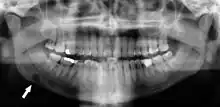

Dental infection and atherosclerosis

Atherosclerosis is attributed to risk factors that include cigarette smoking, hyperlipidemia, obesity, diabetes mellitus, and hypertension (high blood pressure). These factors, however, do not fully account for the risk of disease. Atherosclerosis has been conceptualized as a chronic inflammatory response to endothelial cell injury[24] and dysfunction possibly arising from chronic dental infection. In 2010, using the previously validated Mattila panoramic radiographic index to quantify the totality of dental infection (i.e., periapical and furcal lesions, pericoronitis sites, carious tooth roots, teeth with pulpal caries, and vertical bony defects), Friedlander's group determined that individuals with carotid artery atheromas on their panoramic radiographs had significantly greater amounts of dental infection/inflammation than atherogenic risk-matched controls devoid of radiographic atheromas.[25][26] While the Mattila index had been previously used to relate the extent of dental infection to coronary artery disease, this research is the first to link the full range of dental disease that it measures to panoramic radiographs evidencing calcified carotid artery atherosclerosis.